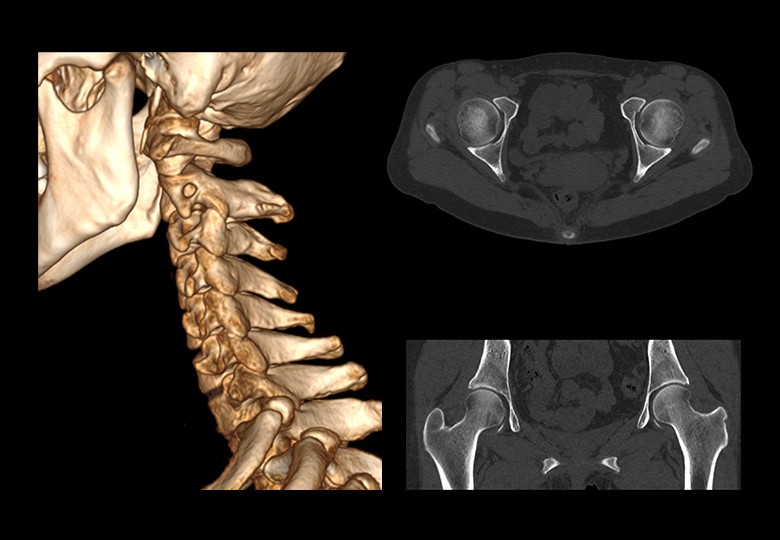

Album d'images cliniques

• Os